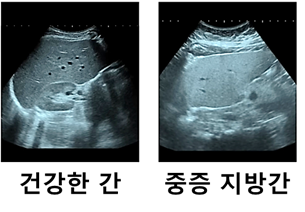

정상 간은 암적색을 띠고 표면도 아주 매끄럽다.

지방간은 약간 노란색을 띠며 간의 크기가 조금 더 증가한 모습을 하고 있다.

지방간은 혈액검사를 통해 수치로 나타낼 수 있고 초음파 검사를 통해 간의 구조, 형태, 혈류를 측정할 수 있다.

초음파 검사에서 지방간이 심하면 간이 하얗게 보인다. 너무 심하면 보여야 할 혈관이 하나도 보이지 않는다.